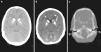

Varón de 10 años, natural de Marruecos, remitido para estudio por discapacidad intelectual. Su hermana mayor también presentaba una discapacidad intelectual de etiología no filiada. Exploración física sin hallazgos, entre los antecedentes personales destaca la existencia de fracturas de repetición. En las pruebas complementarias se objetiva acidosis metabólica (pH 7,196, presión parcial de dióxido de carbono [pCO2]) 42,1mm de mercurio [mmHg], potasio 4 milimoles/litro [mmol/l], gradiente transtubular de potasio 8,47, bicarbonato [HCO3] 15,7 mmol/l, exceso de bases [EB] –11,8 mmol/l) con anión gap plasmático: +10,5 y anión gap urinario 103. Ante la sospecha del origen renal de la misma, se procedió a realizar una prueba de alcalinización de la orina con bicarbonato y acetazolamida, obteniendo en sangre un pH 7,29, pCO2 31,4mmHg y en orina pH 7,87, bicarbonaturia 92 miliequivalentes/l, osmolalidad urinaria 982 miliosmoles/kg y pCO2 de 60,7mmHg, con lo que se obtiene un delta de pCO2 de 29,3mmHg, que podría corresponder con un defecto de acidificación distal. No se valoró la posible afectación en la reabsorción tubular proximal de bicarbonato. La serie ósea (fig. 1) mostraba hallazgos compatibles con osteopetrosis. Dado los antecedentes familiares, se solicita el estudio analítico y radiológico a su hermana (fig. 2) con resultados similares. Ante la sospecha de osteopetrosis asociada a acidosis tubular y la relación de esta con la presencia de calcificaciones intracraneales1,2, se realiza tomografía axial computarizada cerebral con hallazgos compatibles en ambos hermanos (fig. 3). Finalmente se confirma el diagnóstico mediante secuenciación del gen CA2, donde se encuentra la mutación patógenica3 c.232+1G>A en homocigosis en ambos hermanos. No presentaban la sordera que frecuentemente asocia esta entidad1. En la actualidad, se encuentran en tratamiento con bicarbonato asociado a citrato potásico para corregir la acidosis.

TAC cerebral: groseras calcificaciones intracraneales en sustancia blanca, ganglios de la base (a, b) y cerebelo (b). Engrosamiento de la cortical en la calota craneal que invade la esponjosa con desaparición del aspecto de diploe. Esclerosis densa en la base de cráneo que condiciona estenosis en canales nerviosos (c).